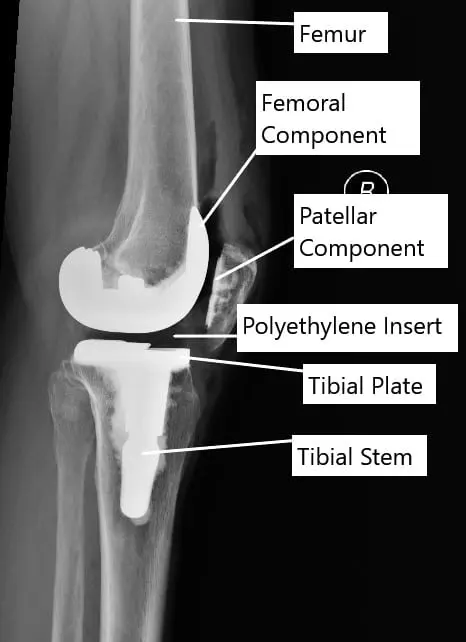

Joint replacement surgery involves replacing/resurfacing the damaged parts of the joint. The forces of the tissues acting on the joints are balanced. The prosthetic/manmade parts are then attached to the resurfaced bone with or without cement.

The prosthetic parts forming the joint may be made of alloys of titanium, cobalt-chromium, polyethylene, ceramic or stainless steel. The prosthetic joint is attached either with special bone cement or is press-fit in the bone. The press-fitted implants allow the bone to grow onto them.